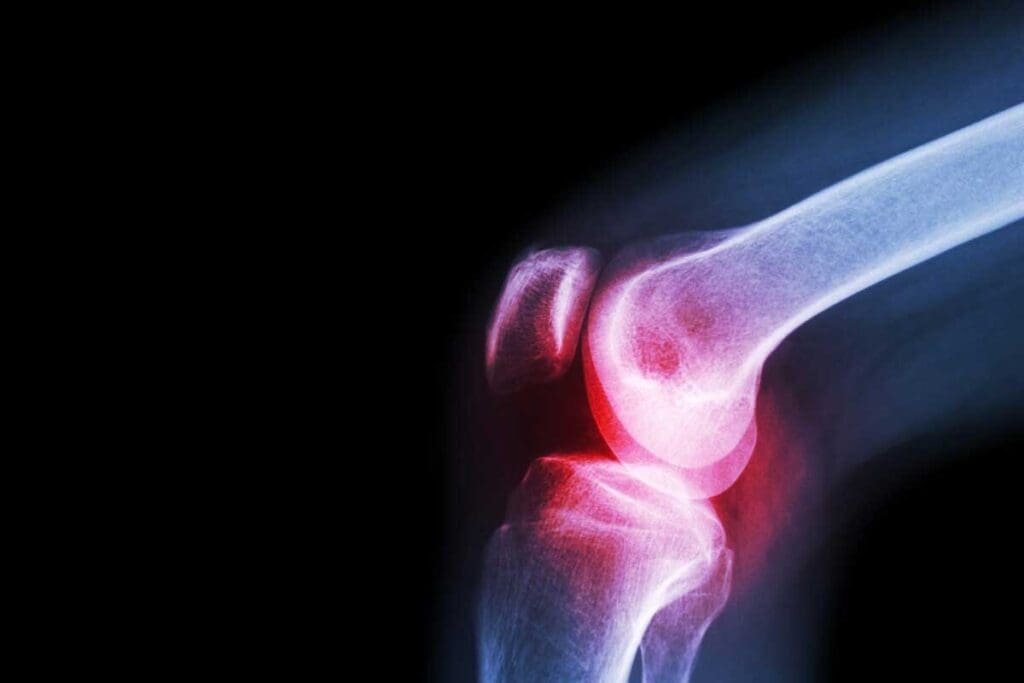

To diagnose, doctors use X-rays, CT scans, and MRI. They also do biopsies. But because it’s so rare in adults, doctors might not think of it right away. This can cause delays.